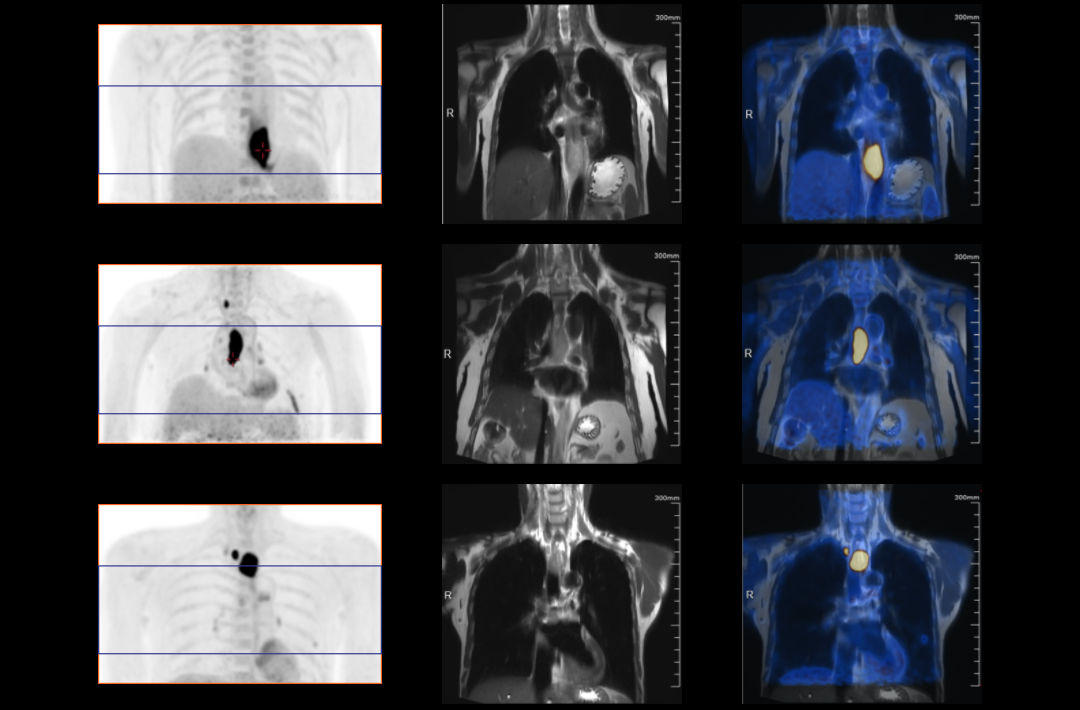

The TNM staging system is currently the most widely used staging system in the world. It can provide relevant information about the location, involvement and spread of the primary tumor through imagological examination methods. It’s one of the most important examination methods to determine cancer staging. Integrated PET/MR perfectly combines molecular functions and structural images and serves as a vital means for the clinical diagnosis of tumors, cardiovascular disease, neurological disease, pediatric disease, and inflammatory disease.

Compared with the conventional PET system with AFOV ranging between 20cm and 25cm, the 32cm long AFOV not only improves the sensitivity of the system, but also basically covers main organs of the whole body and the regional lymphatic system where metastasis may occur, and makes it possible to realize cancer TN staging in one bed position.

In August 2019, Peking Cancer Hospital introduced United Imaging Healthcare's integrated PET/MR to make an in-depth exploration and optimization of cancer TNM staging under long AFOV. More than 500 examples of scanning various organs proved that long AFOV PET/MR could greatly increase the scan range over one bed position and improve the efficiency of cancer TNM staging.

The following are the cases of optimized TNM staging of breast cancer, esophageal cancer, prostate cancer and other diseases under the long axial field of "spatio-temporal integration" ULTRA-clear TOF PET/MR.  Thanks to Capital Medical University Xuanwu Medical Treatment for providing the image.